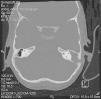

El examen físico revela buen estado general y apirexia. Presenta un aceptable estado de desarrollo y nutrición (peso: 21 kg [P10], talla: 121 cm [P50]). Destaca otorrea izquierda abundante con supuración abierta en la región mastoidea a través de fístula retroauricular (fig. 1), pero no hay signos de tumefacción mastoidea ni adenopatías regionales.

Figura 1.TC craneal: ocupación de todo el oído medio por masa de partes blandas. Las flechas señalan la ruptura de pared mastoidea interna y externa.

Tomografía computarizada (TC) craneal sin contraste con cortes en plano axial a nivel de oído medio con posterior reconstrucción en coronal: oído derecho, normal. Oído izquierdo con masa de partes blandas que ocupa caja, ático, antro y mastoides, con erosión de la cadena osicular. Oído interno, normal. Esclerosis mastoidea con defecto óseo por rotura en la pared externa de la mastoides correspondiente a fistulización retroauricular, y en la pared interna con comunicación a fosa posterior (fig. 1).